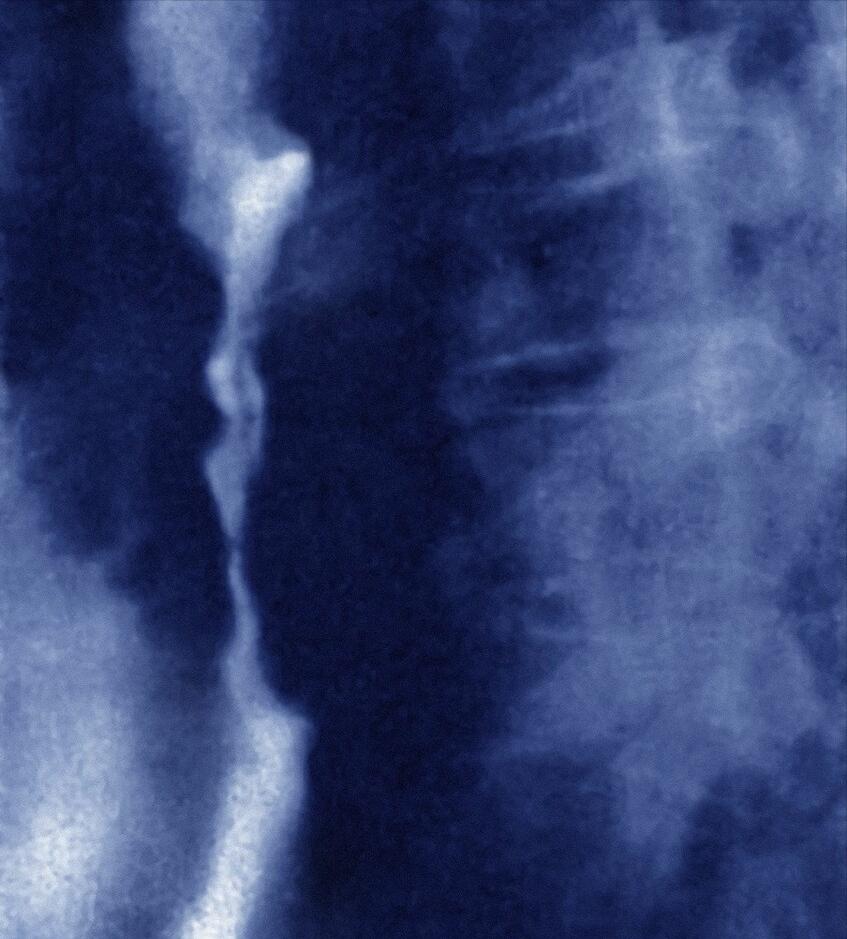

可开始患者拒绝胃镜,反复劝说后同意上消化道钡餐检查。上消化道钡餐,就是喝一些不透X线的钡剂,来看消化道有什么形态和活动的改变。

结果不出所料,钡餐检查报告 中段食管癌,滑动性食管裂孔疝 。